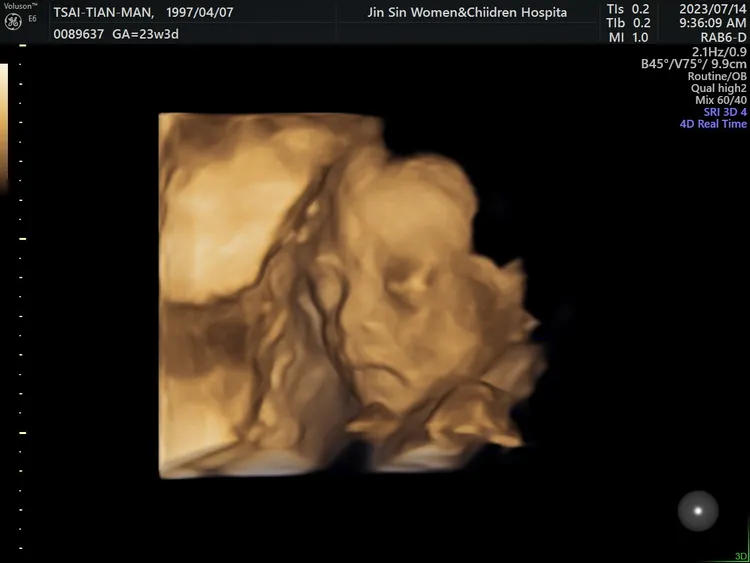

高層次超音波7月中清楚拍下蔡女肚內孩子的輪廓。蔡女提供